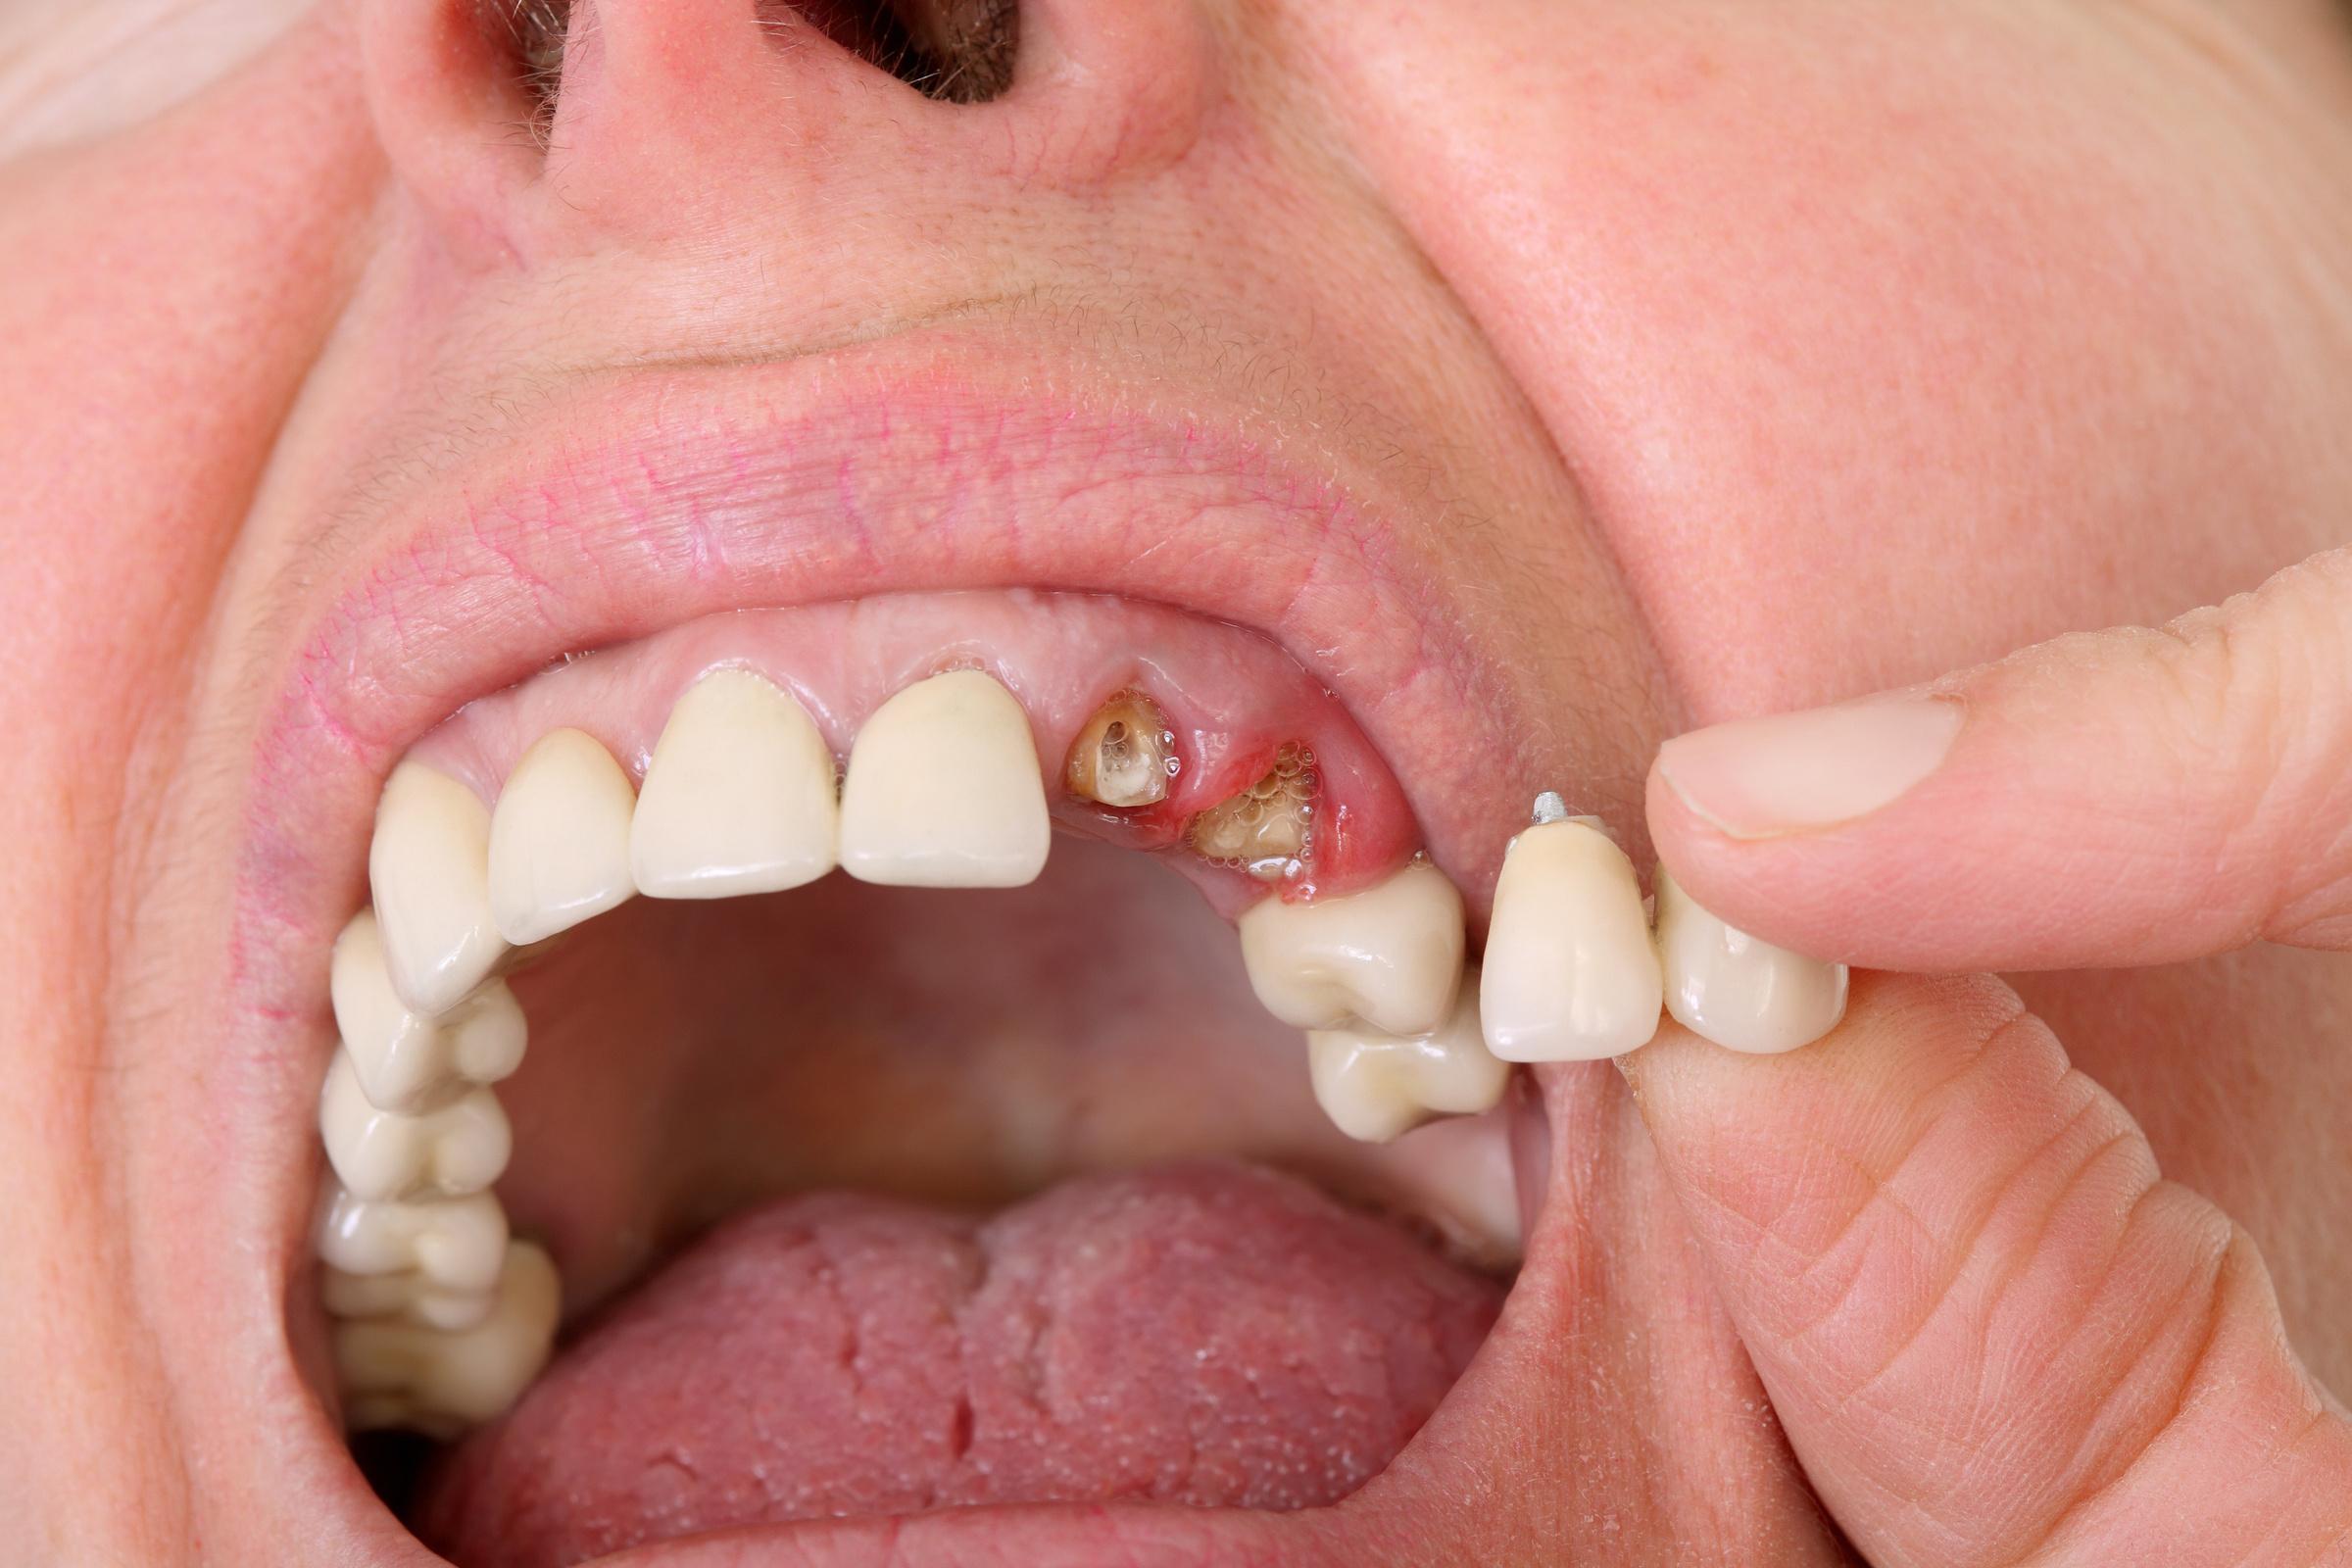

Fractured Tooth or Cracked Tooth: Symptoms, Diagnosis and Treatment

Have you ever experienced sudden and intense tooth pain while chewing or biting down on something? Or perhaps you noticed a small crack in one of your teeth that has been bothering you for a while? These could be signs of a fractured tooth, which can cause discomfort and lead to further dental issues if left untreated.